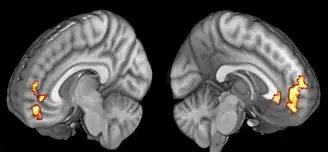

Neural correlates of gratitude. Medial Prefrontal activity correlating with participants' gratitude ratings.